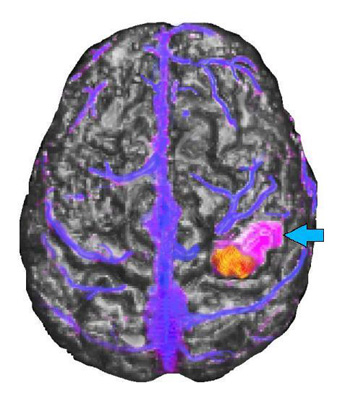

15 year-old right handed girl with sensory-motor partial seizures involving the left hand since the age of 5. MRI showed a focal signal abnormality in the right postcentral gyrus consistent with a developmental tumor without changes over 2 years.

Triple Rendering mid-sagittal top view

MRI of the brain appears in gray scale, functional MR activation is in yellow and red, the tumor is purple (light blue arrow), and the veins are blue. The tumor appears located in the post-central gyrus lateral and rostral to the functional activation. The relationship between the tumor and the functional activation was confirmed during awake intraoperative mapping. The venous landmarks provided useful information to the operating surgeon. The patient's tumor was removed without residual monoplegia. The patient had only transient loss of stereognosis and proprioception involving the 3rd, 4th, and 5th fingers, post-operatively.